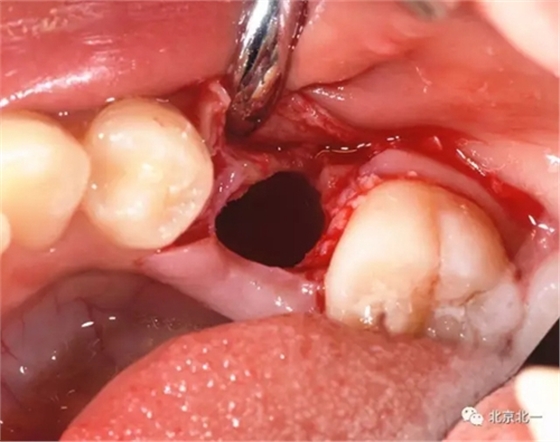

拔牙前臨床照片

術(shù)中有絲分裂

埋伏牙專用攪碎機攪碎牙齒

總結(jié):埋伏牙如果直接硬撬可能會導致牙槽骨骨折。需要采用微動力系統(tǒng)將牙齒有絲分裂后拔除。